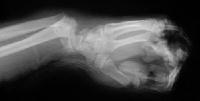

Xrays at the beginning and end of the distraction process.